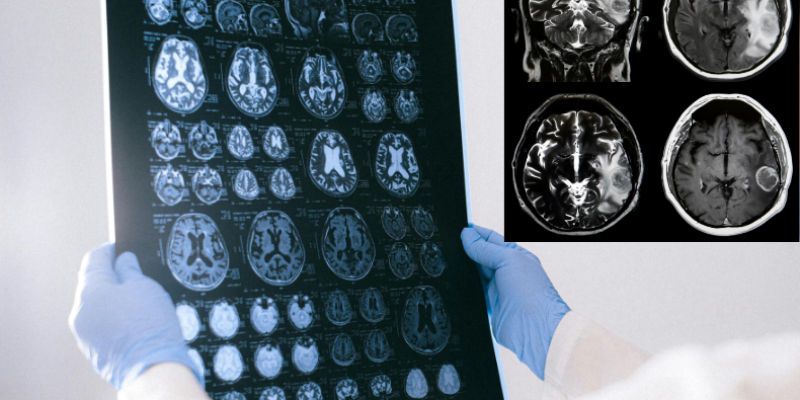

MR Görüntüleme — İlk Adım

Beyin tümöründen şüphelenildiğinde öncelikle kontrast madde ile MR (manyetik rezonans görüntüleme) çekilir. Bu inceleme tümörün yerini, büyüklüğünü ve çevresindeki dokuya etkisini gösterir.

Bunun yanı sıra günümüzde şu ileri görüntüleme yöntemleri de sıklıkla kullanılmaktadır:

• Difüzyon MR: Tümör içindeki hücre yoğunluğunu değerlendirir.

• MR Spektroskopi: Tümörün metabolik profilini çıkarır, düşük-yüksek derece ayrımında yardımcı olur.

• DTI (Difüzyon Tensör Görüntüleme): Traktografi ile kritik sinir yollarını haritalayarak cerrahi planlamayı kolaylaştırır.

• PET: Tümörün metabolik aktivitesini gösterir.